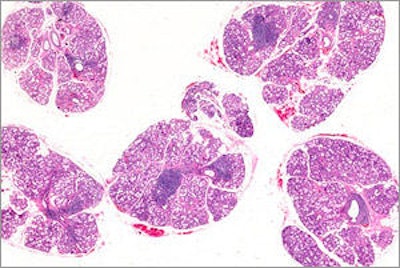

Photomicrograph of a salivary gland with sites of inflammation indicative of Sjögren's syndrome. Image courtesy of NIDCR.

- Salivary gland biopsy: A pathologist examines the biopsy for sites of inflammation. One or more sites of inflammation per 4 mm squared area is considered positive.